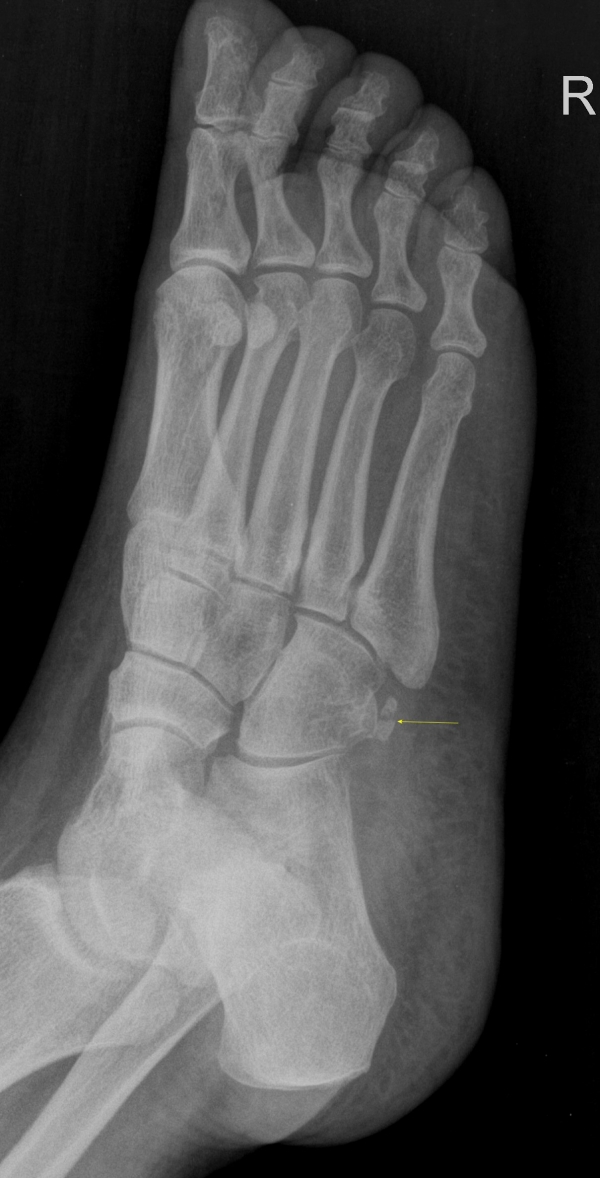

´Ü¼ø¹æ»ç¼±°Ë»ç

ºñ°ñ°ÇÀÇ °ñÀýÀÌ ÃßÁ¤µÇ´Â ¾ç»ó